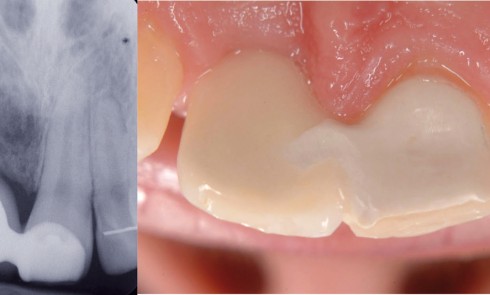

Malgré l’amélioration de la santé orale observée dans les pays industrialisés ces dernières années, l’extraction dentaire reste un acte fréquent....

La mise en place de restaurations prothétiques unitaires sur des implants situés dans les secteurs postérieurs (zone des prémolaires et...